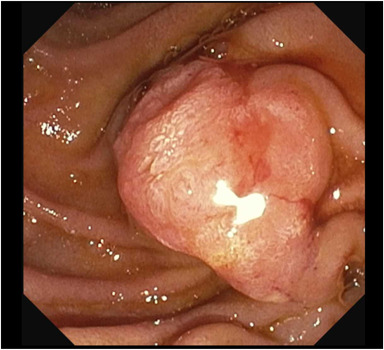

An Original Article by Netanel Zilberstein describes "Characterizing the extent and morphology of intraductal mucinous biliary neoplasm using a novel cholangioscope and treatment with ampullectomy." videogie.org/article/S2468-… Nati Zilberstein Neal Mehta Kara Raphael

Honored to have had the opportunity to publish our case in this month’s videogie. Neal Mehta